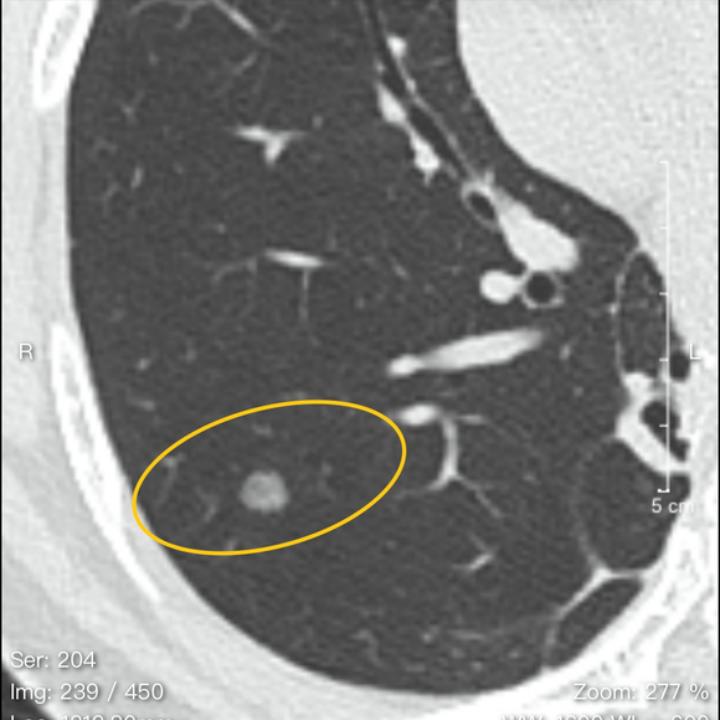

今天的这位结友,2020年初发现右肺的磨玻璃结节和“实性结节”(这里实性结节我打了引号,因为当时医生出现了判断失误,把混磨看成了实性结节)。2021年4月手术切除了磨玻璃结节,但在后期的复查,留下的“实性结节”始终无法精准诊断。到了今年,结节长大,当地医院忽然又建议手术。这可吓坏了这位结友,好好地咋忽然又要手术了?

于是来贴吧找我,希望我给个精准诊断。从片子上看来,这个混磨已经发展成微浸润腺癌或浸润性腺癌的状态,还可能需要手术。

女,51岁,工作环境良好。2020年元月体检发现右肺1.2cm磨结和5mm实性结节,2021年4月切除大磨,1A1期。5mm实性小结节随访,其间有消炎和服中药2年,多次复查改报磨结,今年4月复查CT提示长大了,门诊意见可随诊可切除,令人不知所措,心忧不已。

这哪是实性结节?接近实性结节而已,典型的混磨,第一次次手术大小兼顾,带掉就好了。

至少微浸润腺癌,楔形切除小手术还可以根治。